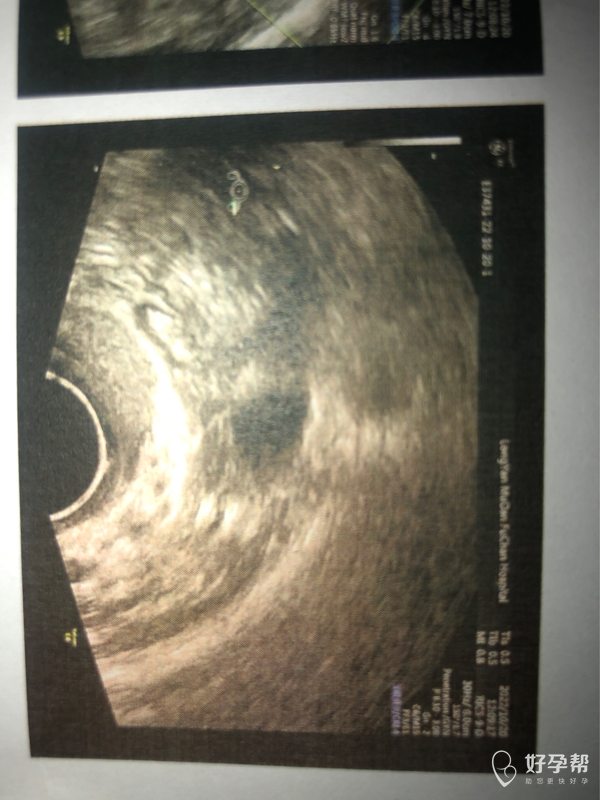

医生好这是我月经第8天的阴道彩超图请问按图上

可以继续观察子宫内膜厚度、形态、血流等。月经第8天,时间短,建议继续监测子宫情况。